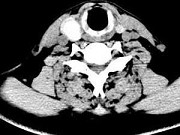

- 单项选择题男,43岁, 右颈部扪及一包块,CT如图所示, 最可能的诊断是 ( )

A、甲状腺腺瘤

B、甲状腺腺癌

C、结节性甲状腺肿

D、甲状腺原发淋巴瘤

E、甲状腺转移瘤